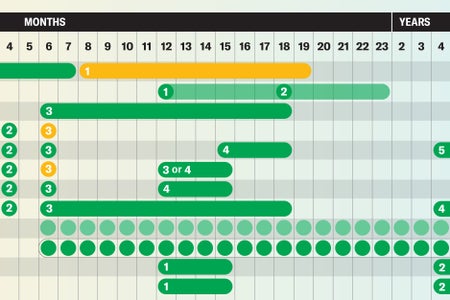

See Vaccine Recommendations Backed by Science in These Handy Charts

These graphics will guide you through science-based vaccine guidelines for children and adults